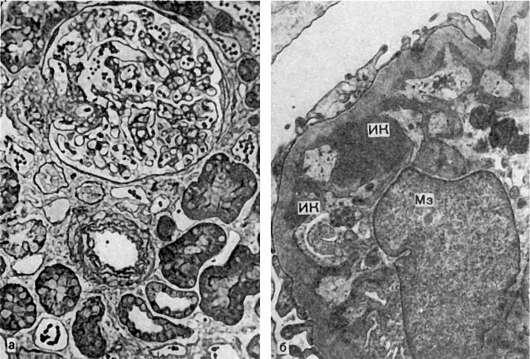

Рис.

227.Мезангиопролиферативный гломерулонефрит:

а - пролиферация мезангиальных клеток, расширение мезангия, полутонкий срез (гистологическая картина); б - гипертрофия мезангиоцитов (Мз), отложение иммунных комплексов (ИК) в мезангии. Электронограмма. х12 000